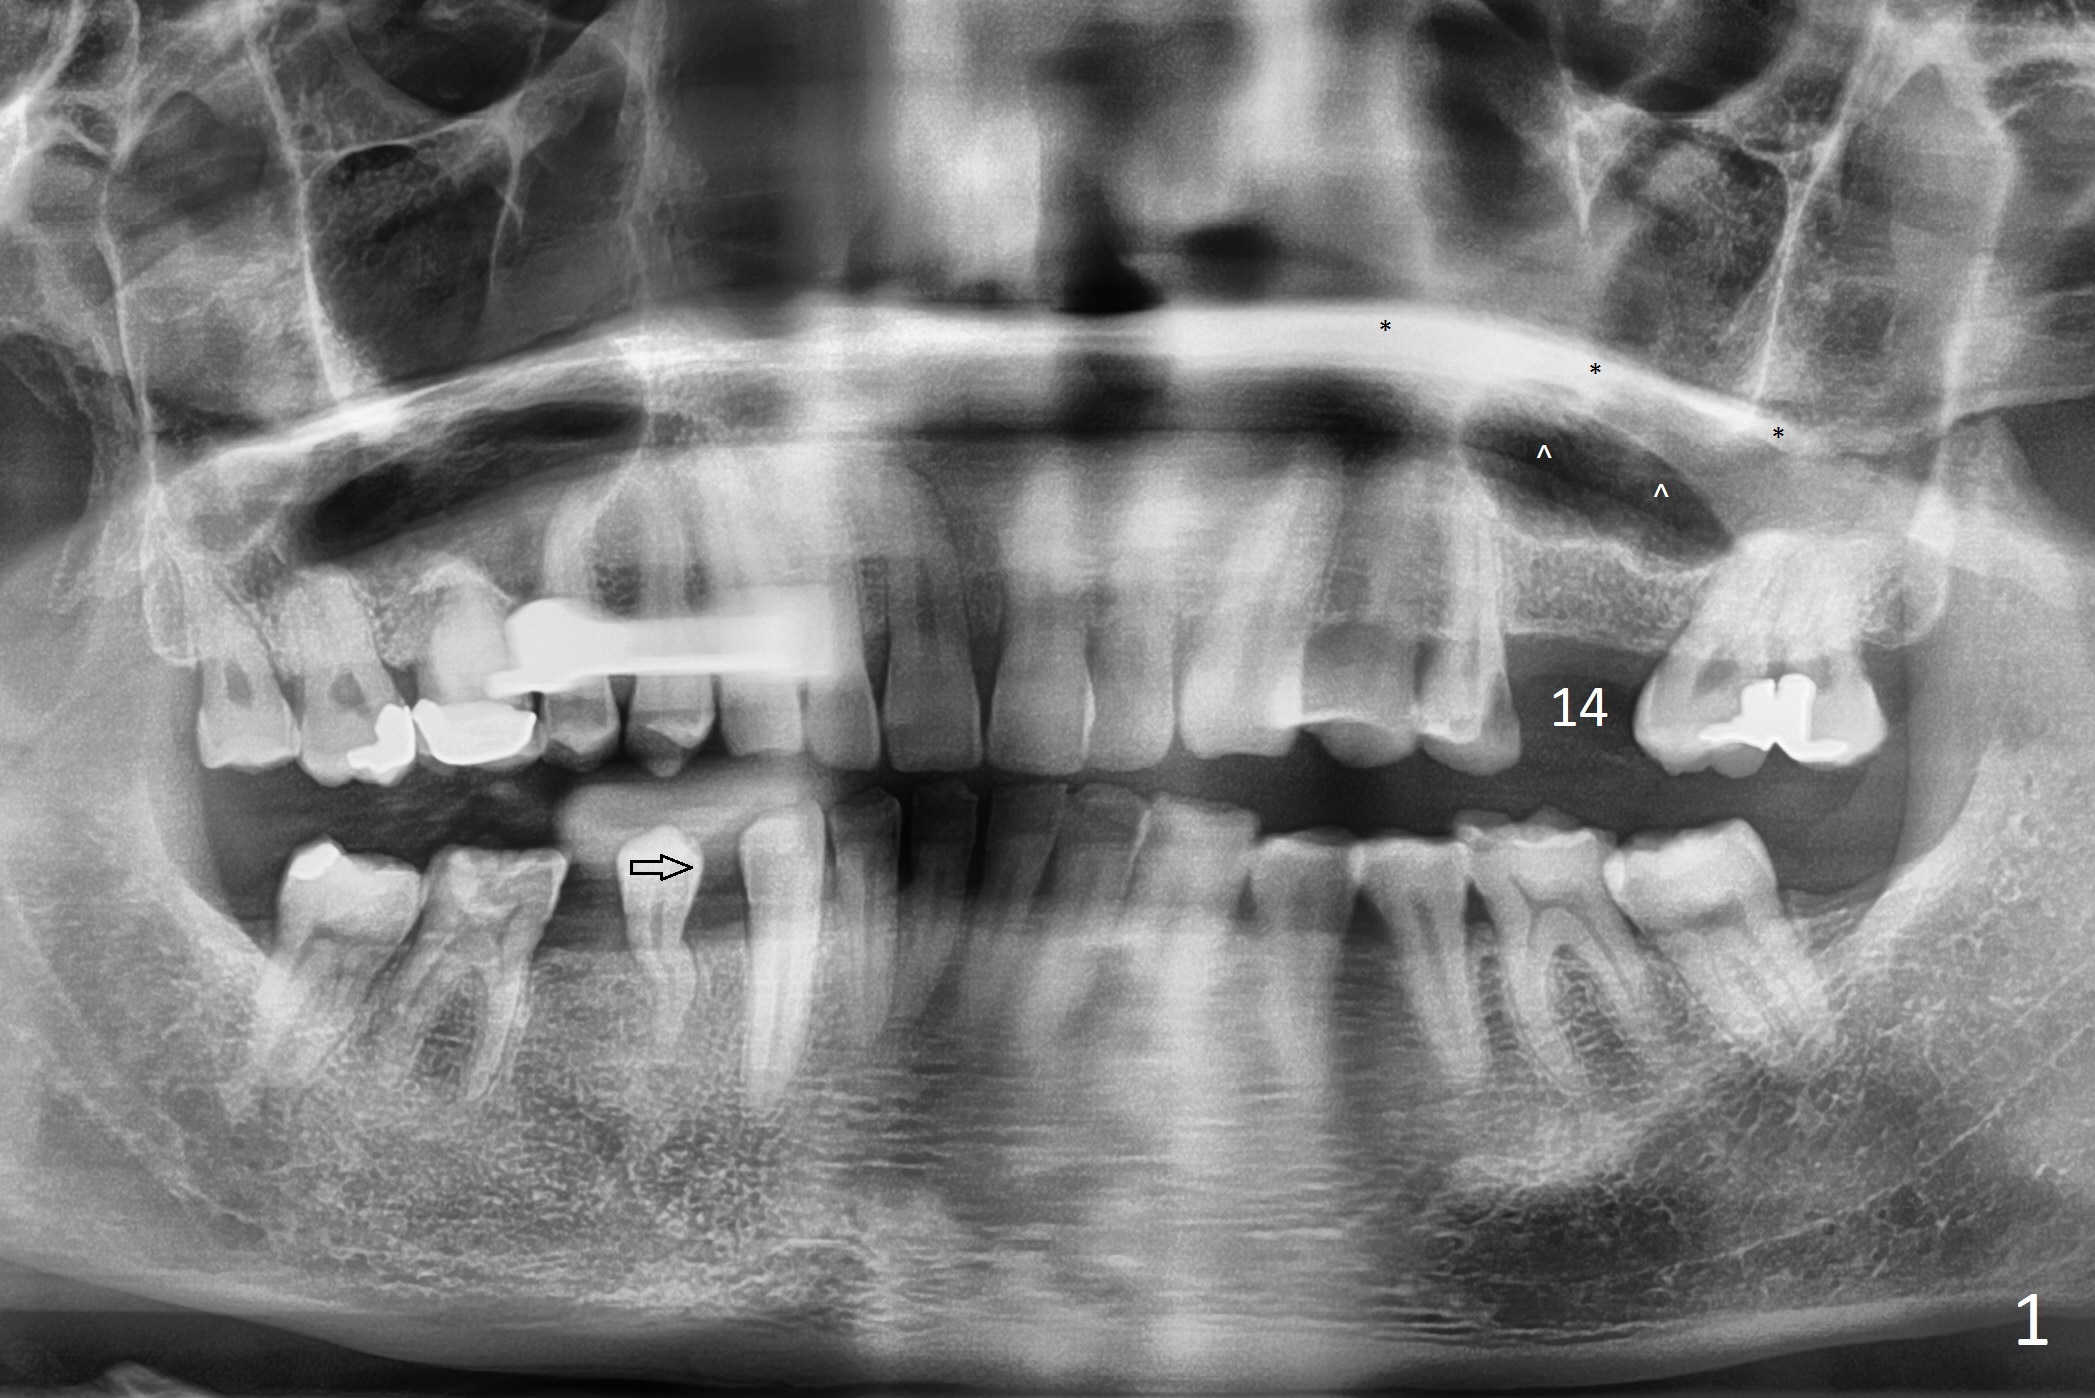

Place Implant Between Two Layers of Sinus Floor

A 47-year-old man agrees implant at #14 (Fig.1). He worries about the bone height. There appear to be 2 layers of the sinus floor (Fig.1,2 (arrowheads: upper one)). The horizontal plate of the palate is indicated by *. An IBS implant will be placed between the 2 layers of the sinus floor as shown in Fig.3. Osteotomy is initiated with Magic Split, followed by Magic Expanders (initial depth 9 mm gingival level) or Magic Lifter. Before placing the implant, insert PRF and Allograft with a condenser with a stopper.